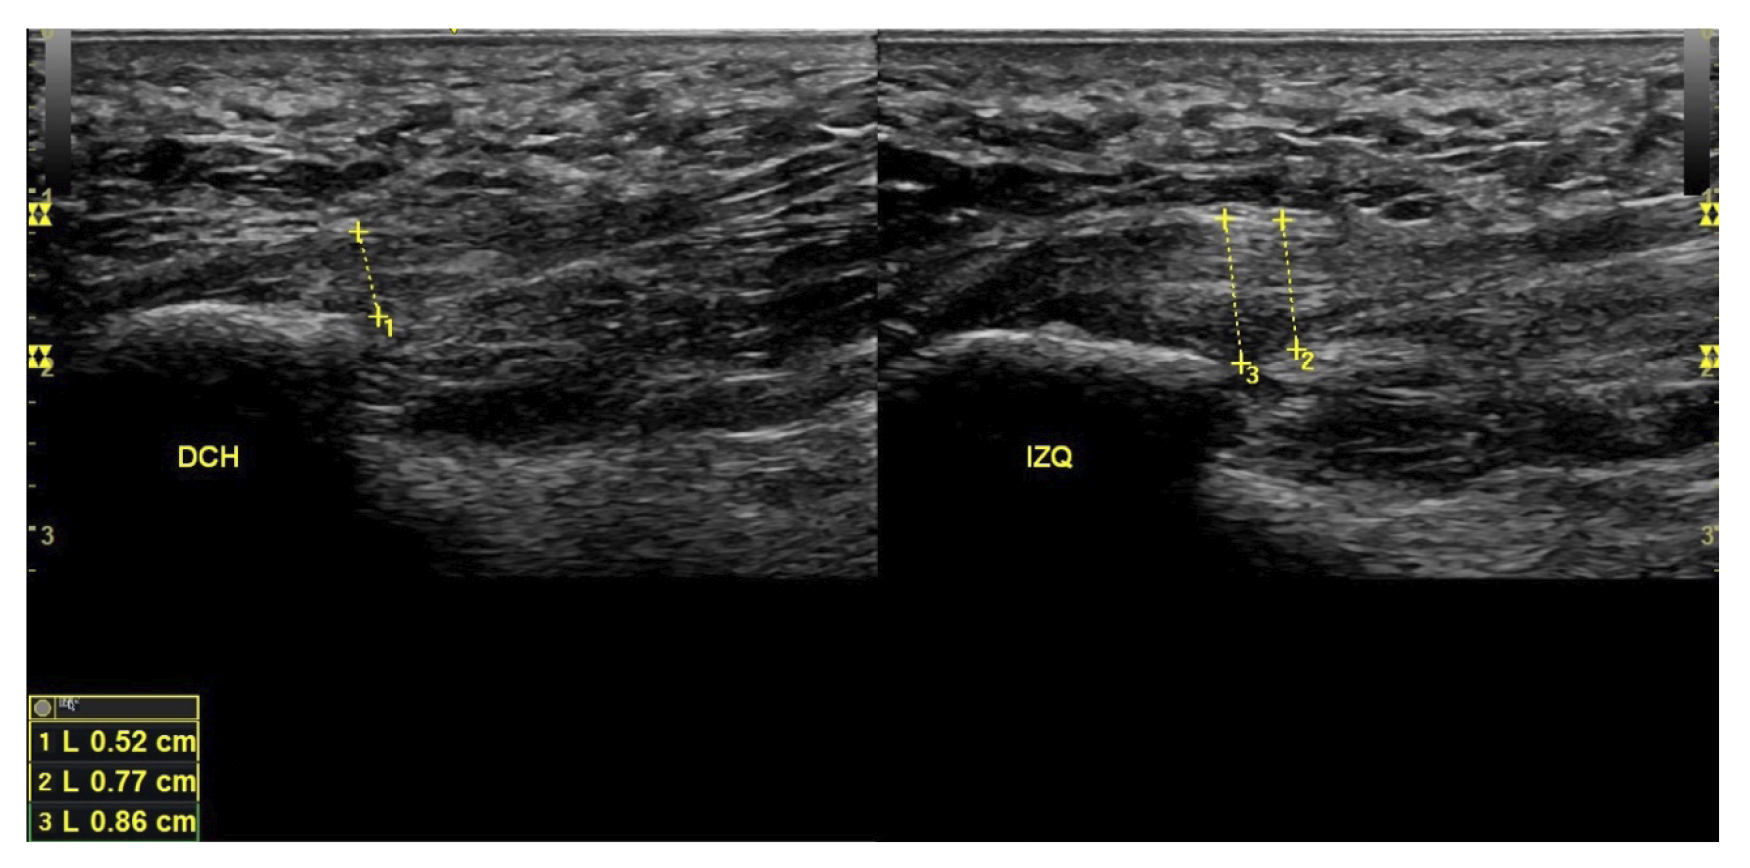

El diagnóstico se estableció en base a los síntomas y se confirmó mediante ecografía con equipo de alta resolución (Alpinion Ecube 9, ALPINION MEDICAL SYSTEMS Co., Ltd., República de Korea) con transductor lineal de 6 a 12 MHz (Figuras 2 y 3).

Figura 2. Investigador con la sonda lineal para la medición del grosor de la fascia plantar.

Figura 3. Área de medición del grosor de la fascia plantar. La línea punteada corresponde con la medición del grosor.